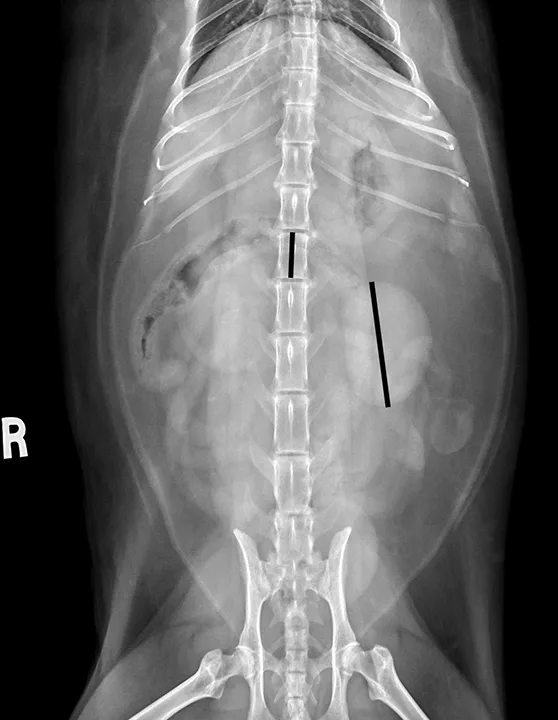

Kidney size varies between intact and neutered male cats.9 On ventrodorsal radiographs, normal kidney:L2 ratios are 1.9 to 2.6 (measuring renal length and dividing by the length of L2) in neutered male cats and 2.1 to 3.2 in intact cats (Figure 5).9

FIGURE 5

Ventrodorsal radiograph measuring renal size of normal kidneys in a neutered cat. The longer black line over the renal silhouette shows the length of the left kidney, which can be compared with the shorter black line superimposed on the L2 vertebral body.